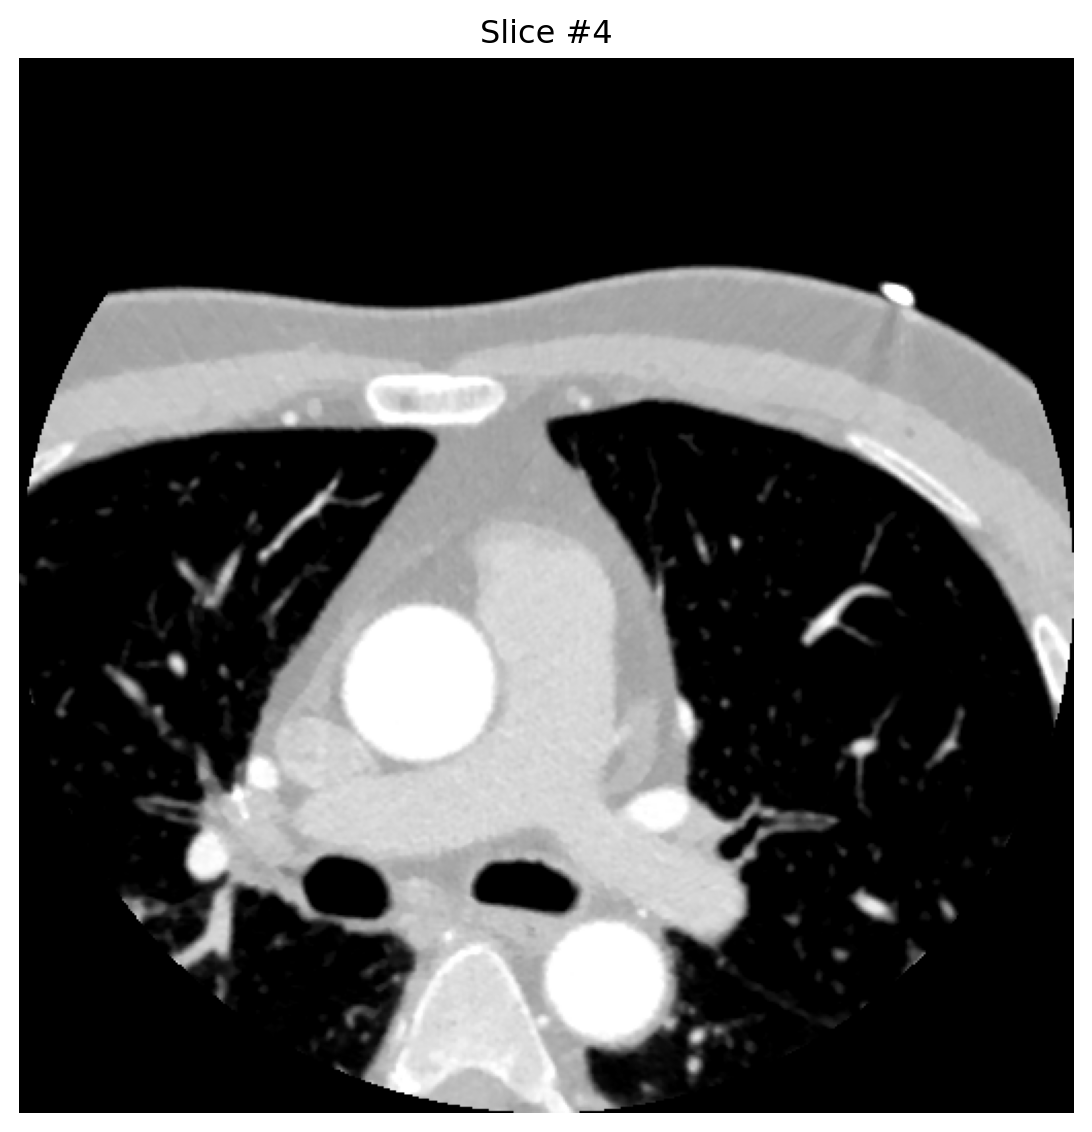

2.2. Processing + Visualization

def analyze_dicom_slice(slice_index):

buffer = BytesIO(dcb_stream.get_dicom_for_frame(slice_index))

dataset = pydicom.dcmread(buffer, force=True)

pixels = dataset.pixel_array.astype('float32')

if hasattr(dataset, 'RescaleIntercept'):

pixels += float(dataset.RescaleIntercept)

plt.figure(figsize=(8, 6))

plt.imshow(pixels, cmap='gray', vmin=-800, vmax=300)

plt.axis('off')

plt.title(f"Slice #{slice_index}")

plt.tight_layout()

plt.show()

return dataset

for idx in [0, 4, 8]:

analyze_dicom_slice(idx)

Conversion happens only when requested—no need to pre-expand entire series, saving space and latency.